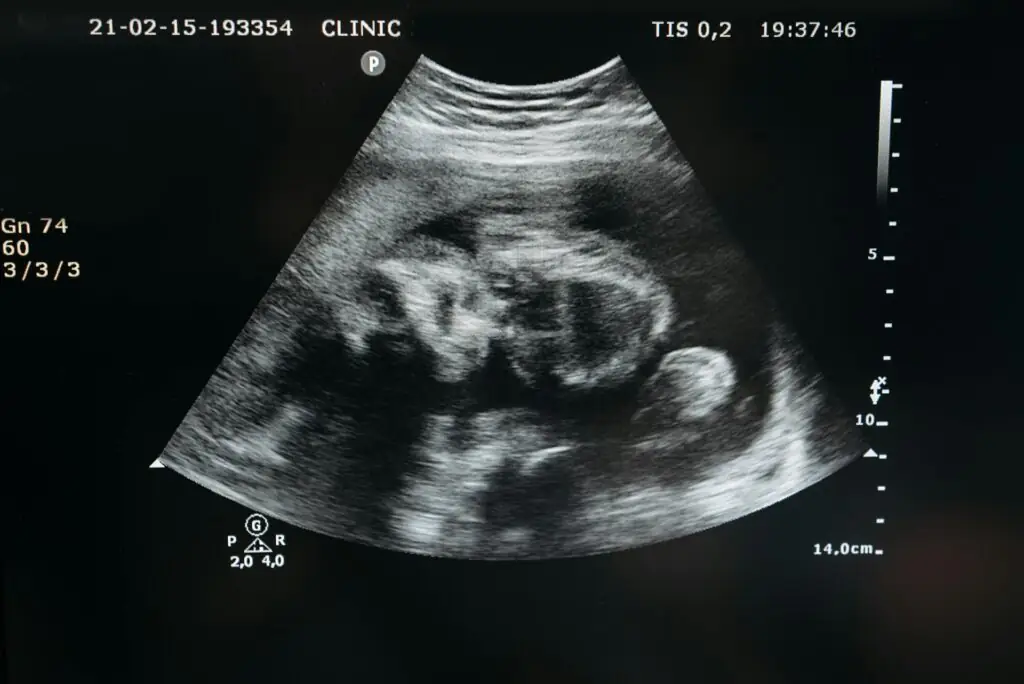

2. Segundo Trimestre (Semanas 13 a 26)

Crescimento Acelerado

- O feto cresce significativamente, alcançando cerca de 30 cm ao final desse período.

- A pele, inicialmente translúcida, começa a se revestir de vérnix caseoso, uma substância que protege contra o líquido amniótico.

Desenvolvimento Sensorial

- Semanas 16-20: O feto desenvolve sentidos como tato e audição. Ele pode ouvir a voz da mãe e reagir a sons externos.

- Semanas 21-24: Os pulmões começam a produzir surfactante, essencial para a respiração após o nascimento.

Movimentos Perceptíveis

- A mãe começa a sentir os chutes e movimentos do bebê.